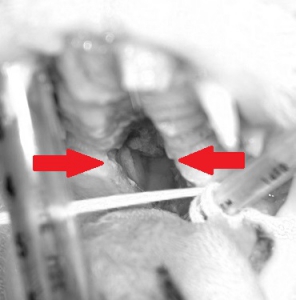

左の写真は右下からの正面像で、上顎の歯の後ろから喉に至る部分が完全に避けて鼻の穴の奥が口から見えていしまっている状態です。右写真は裂けてしまった上顎の断面が痛々しい写真です。ここまで重度のものになるとまったく食事を摂ることができないだけではなく呼吸の障害も生じるため、早急に手術が必要になります。